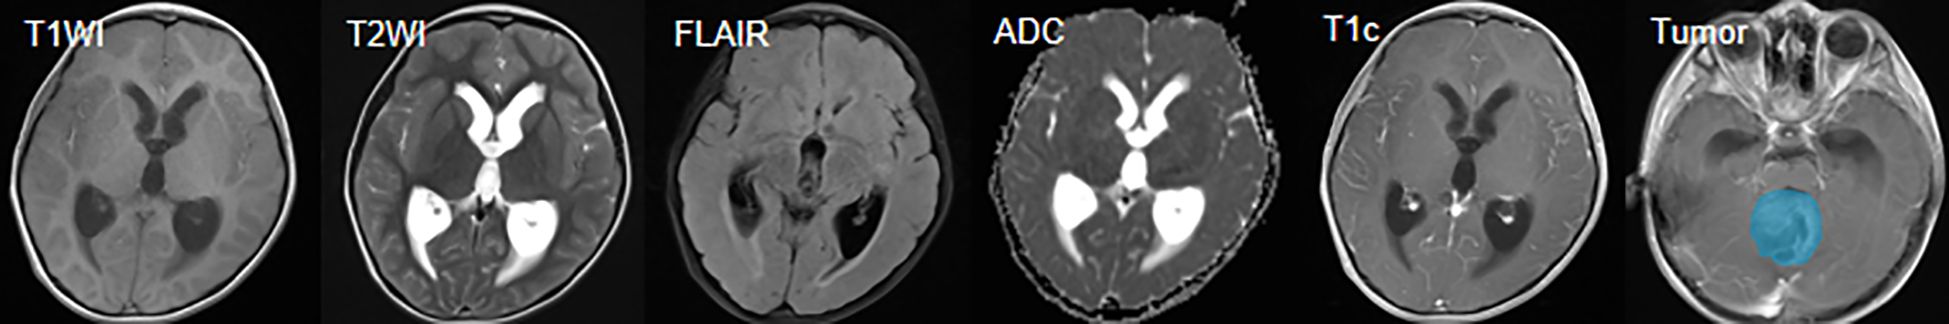

Background: The MRI imaging traits of pediatric posterior cranial fossa neoplasms overlap highly, leading to difficulties in preoperative diagnosis. Their treatment strategies differ significantly, and traditional deep learning models have limitations in multi - sequence MRI fusion and clinical interpretability, so new solutions are urgently needed. Objectives: This study aims to develop a 2.5D multi - sequence MRI deep learning framework (ResSwinT) that integrates Residual Network and Swin Transformer, to achieve automatic classification of three main Pediatric posterior fossa tumors—Pilocytic astrocytoma (PA), Medulloblastoma (MB), and Ependymoma (EP), and enhance the interpretability of the model through the SHAP method, so as to provide a more reliable auxiliary decision-making basis for clinical practice. Methods: This study retrospectively collected 309 pediatric patients confirmed by pathology, including 109 PA, 130 MB and 70 EP. The MRI data of these patients included five sequences: T1WI, T1C, T2WI,FLAIR , and ADC. After preprocessing steps such as N4 bias field correction, resampling, sequence registration, and intensity normalization, samples were constructed using a 2.5D image construction strategy, and the ResSwinT model is designed. Its performance was compared with seven deep learning models such as Residual Network 18 and VGG16, and SHAP analysis was used to analyze trait contributions. Results: The proposed ResSwinT model outperforms existing commonly used deep learning models in all classification tasks, particularly showing outstanding performance in terms of area under the curve(AUC) and overall accuracy(ACC). For the PA vs Non-PA task: ACC 89.5%, AUC 0.975; for the MB vs Non-MB task: ACC 93.7%, AUC 0.978; for the EP vs Non-EP task: Acc 87.5%, AUC 0.937. SHapley Additive exPlanations(SHAP) analysis shows that the model pays high attention to the gross tumor volume and its surrounding structures, and its decision-making basis is highly consistent with key imaging biomarkers, verifying the interpretability and clinical relevance of the model. Conclusions: ResSwinT achieves high-precision classification of pediatric posterior fossa tumor through 2.5D multi-sequence fusion and cross-attention mechanism. SHAP attribution analysis reveals the biological basis of the model's decision-making, providing clinicians with an interpretable AI-assisted diagnostic tool, and is expected to optimize individualized treatment strategies.